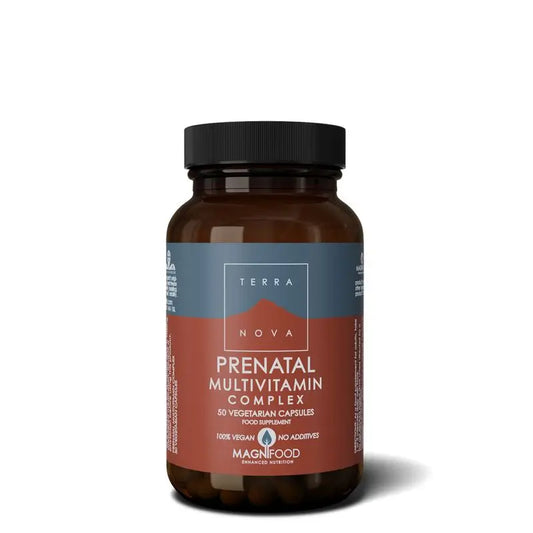

En la lactancia, el cuerpo de la madre está haciendo un trabajo increíble al proporcionar todos los nutrientes necesarios para el bebé, es por eso que un apoyo nutricional en esta etapa es clave para el correcto desarrollo del peque.

Aunque muchas de estas vitaminas y minerales, como vitaminas del grupo B, C, D o hierro, calcio y ácido fólico, los podemos encontrar en determinados alimentos, existen vitamínicos para la lactancia que van a aportar ese soporte que tanto la mamá como el peque necesitan.

Como mencionábamos al principio del post, en la lactancia el cuerpo de la madre trabaja sin descanso para proporcionar los nutrientes necesarios para el bebé.

Un complemento vitamínico para la lactancia que va a ayudar ambos es Femibion 3 Lactancia, ya que contiene en su fórmula múltiples vitaminas y minerales claves para el bienestar de la lactante y desarrollo normal del peque, además de aportarle todos los nutrientes que necesitan.

Se recomienda tomar 1 comprimido durante el periodo en el que se de el pecho y, como mínimo un mes. Aunque siempre bajo recomendación médica.